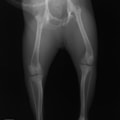

■ 症例24 キャバリア 7か月

左右膝蓋骨内方脱臼(左:グレードⅣ 右:グレードⅢ)

以前から左右後肢の跛行が認められ、整形外科学的検査・レントゲン検査により左右の膝蓋骨脱臼が認められた。症状が重度である左膝の膝蓋骨脱臼整復術を行った。外科手技は縫工筋及び内側広筋の解放、脛骨粗面の外側転位、滑車ブロック形造溝術、内外側関節方の縫縮を実施した。術後一か月時点で、左の膝蓋骨は安定しており経過は良好である。

本症例は成長期における重度の膝蓋骨脱臼であり、術後の再発の可能性もあるため、経過をしっかりと観察していく必要がある。また、今回手術を実施していない右膝に関しても経過を観察し、手術を検討していくこととする。